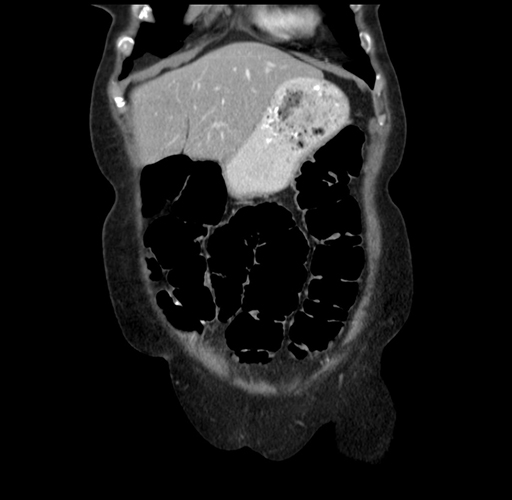

Pre-Chemo: Axial Venous

Pre-Chemo: Coronal Venous